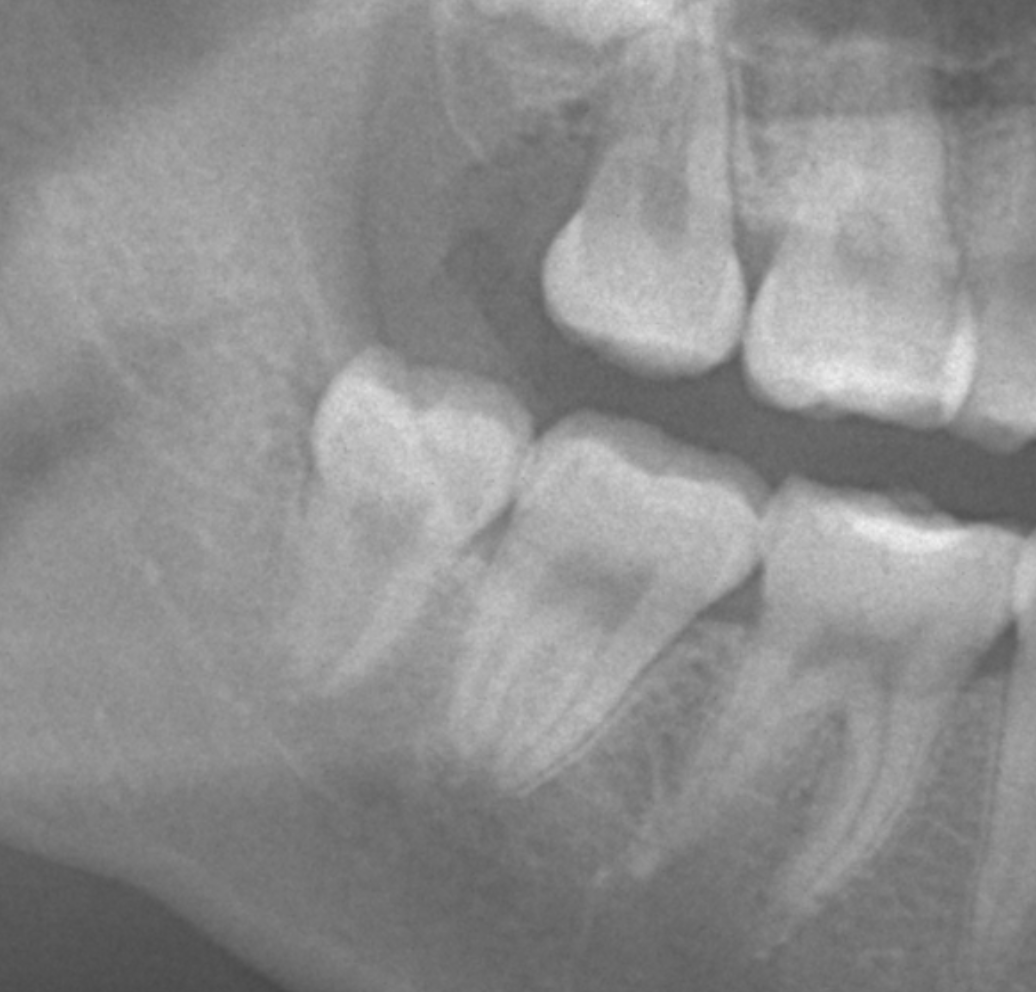

まっすぐ生えている場合は簡単な抜歯で済みますが、横向きや骨の中に埋まっている「埋伏歯」の場合は外科的処置が必要となります。

骨や歯ぐきの中に埋まっている「埋伏歯」は、腫れ・膿み・口臭の原因になることもあります。

当院では歯科用CTによる精密検査を行い、リスクを最小限に抑えた計画的な抜歯を行います。